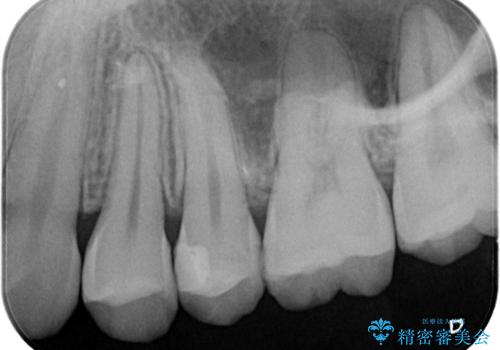

- 定期検診にてむし歯を認めたため、セラミックインレーにて修復を行いました。

e-max プレスインレーにて修復治療を行っているため適合性及び審美性の高い治療を行うことができます